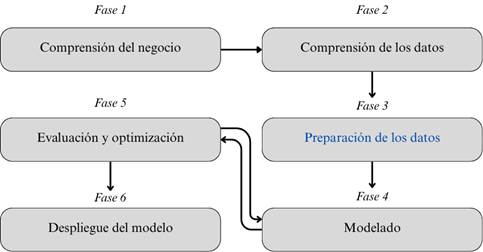

Este estudio adoptó la metodología CRISP-DM, reconocida como el modelo estándar para la implementación de proyectos de minería de datos. Su estructura se compone de seis fases: comprensión del negocio, comprensión de los datos, preparación de los datos, modelado, evaluación y despliegue. Las fases se relacionan y permiten una aproximación iterativa y flexible al análisis de datos, adaptándose a las necesidades específicas de cada proyecto (Schröer et al., 2021). Su aplicabilidad en contextos de salud ha sido validada en investigaciones recientes, donde ha guiado con éxito el desarrollo de soluciones basadas en Machine Learning para la detección de enfermedades (Tamayo y Sauñe, 2024). El seguimiento de la metodología CRISP-DM para el entrenamiento de los modelos, se ha diseñado siguiendo los fundamentos de la figura 1.

Figura 1. Metodología CRISP-DM.

Elaboración: Los autores.